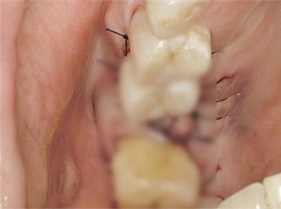

잇몸 봉합 (3~5개월 후 완성)